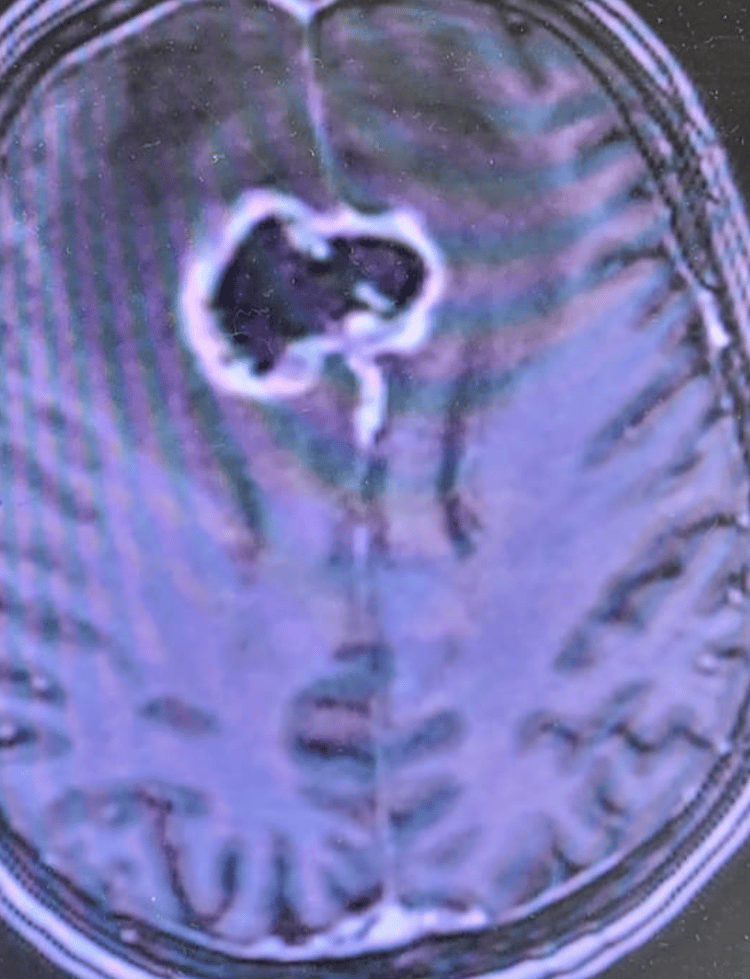

I'm Dr. David Wasilewski, a senior neurosurgery resident (PGY-6) at University Hospital Düsseldorf, with prior training at Charité – Universitätsmedizin Berlin and a research fellowship at CNIO Madrid. My clinical and scientific focus lies in glioblastoma, lower-grade gliomas, brain metastases, and general neurosurgery. I’ve contributed to multiple peer-reviewed publications (H-index 9), co-supervised doctoral theses, and led or co-led translational research projects in neuro-oncology across Europe. Furthermore I am interested in patient education and conveying information from the neurooncology community to a broader public. This site shares selected educational resources for patients/relatives and also doctors in terms of specific topics in neurooncology and neurooncology practice.